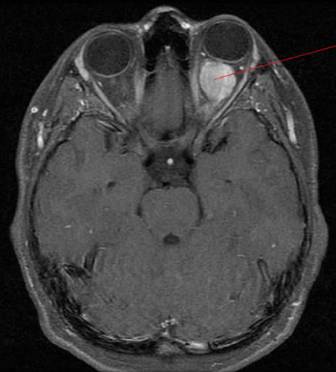

Очень важно при постановке диагноза отличить глиому от минингиомы. Самым точным исследованием, позволяющим безошибочно определить наличие глиомы даже на первоначальной стадии, является проведение КТ головного мозга. Оно позволяет провести визуализацию утолщения зрительного нерва, определить степень активности распространения опухоли и ее прорастания в черепную область. Если не представляется возможности пройти компьютерную томографию, тогда человека направляют на рентгенографию черепной области и орбиты.